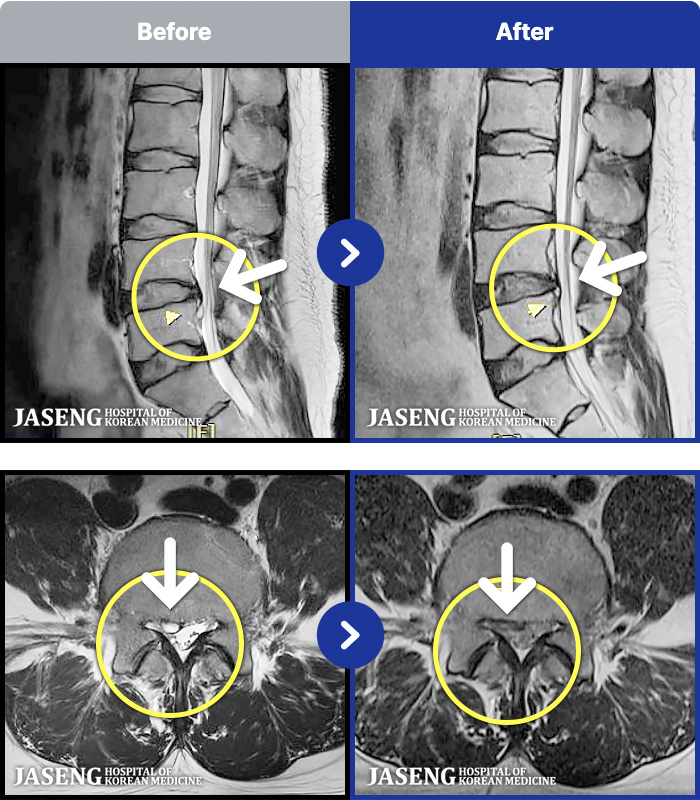

MRI ġ

1,237 MRI ũ ʸ Ȯϼ.